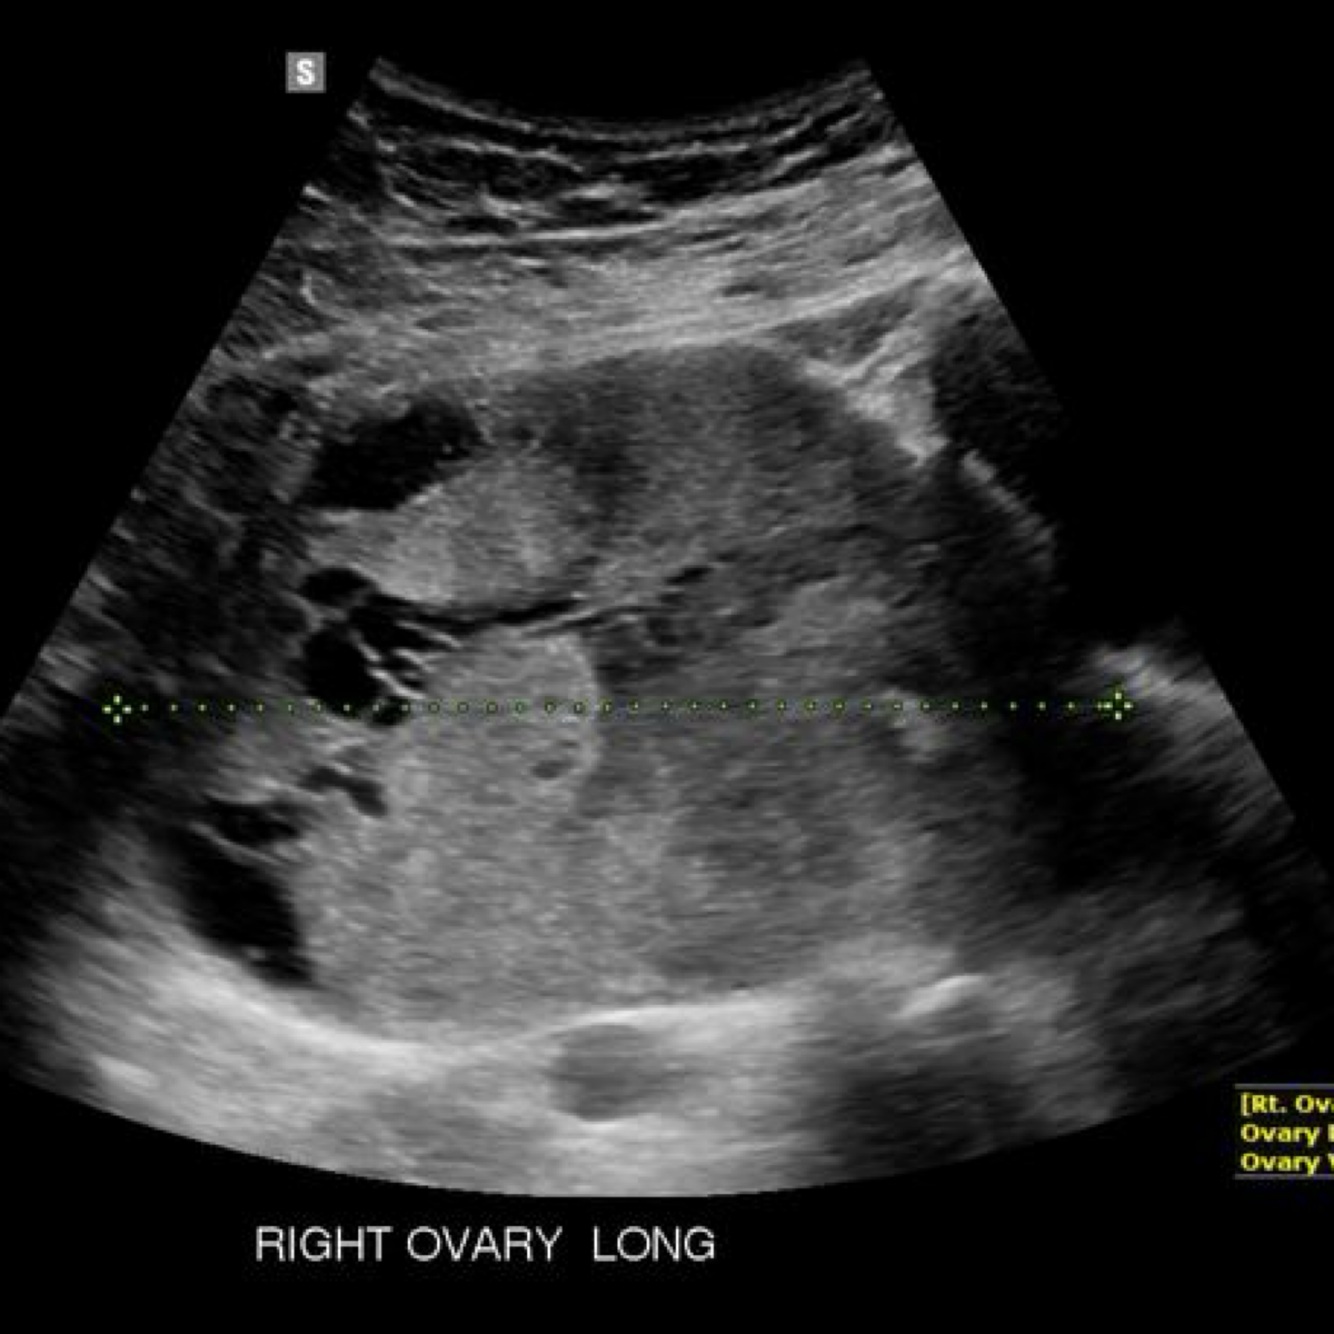

is a malignant germ cell tumor of the ovary, and it is the most common malignant germ cell tumor in young females. It is histologically identical to testicular seminoma. Slow growing

–solid OVARIAN MASS, lobulated, hypervascular

–possible necrosis, septa, calcifications

–abdominal distension and pain, menstrual irregularities

–lab elevated hCG, AFP, LDH

Dysgerminoma